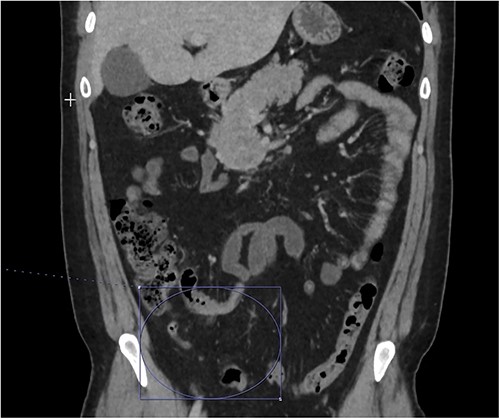

At home, the patient continued to do well and remained free of abdominal pain. He was tolerating a normal diet without emesis and was having normal bowel function. His outpatient CT scan 3 months after discharge demonstrated near resolution of his subocclusive PV and SMV thrombus and attenuated periappendiceal inflammation (Figs 3 and 4). Given the patient’s clinical stability and benign radiographic findings, the patient was scheduled for a laparoscopic appendectomy.

Only a slender portion of thrombus remains in the main portal vein; the previously seen splenic vein thrombosis has largely resolved (not well visualized).